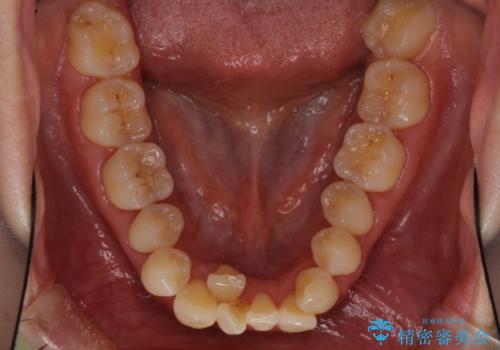

前歯のデコボコを治したい 費用を抑えた抜歯矯正

- 上下前歯のでこぼこを気にされ、矯正治療を希望された患者様です。

費用を抑えるため、メタルブラケットを採用し、抜歯矯正を行うこととしました。

通常であれば、上下顎左右小臼歯各1歯の合計4本を抜歯しますが、歯肉退縮の著しい下顎前歯を抜歯して欲しいという患者様の強い希望により、上顎のみ左右小臼歯2歯を、下顎は前歯を1歯を抜歯することとしました。

抜歯する歯を変更したため奥歯の咬合はアンバランスとなりましたが、前歯は綺麗に整い、歯肉退縮も回避できました。